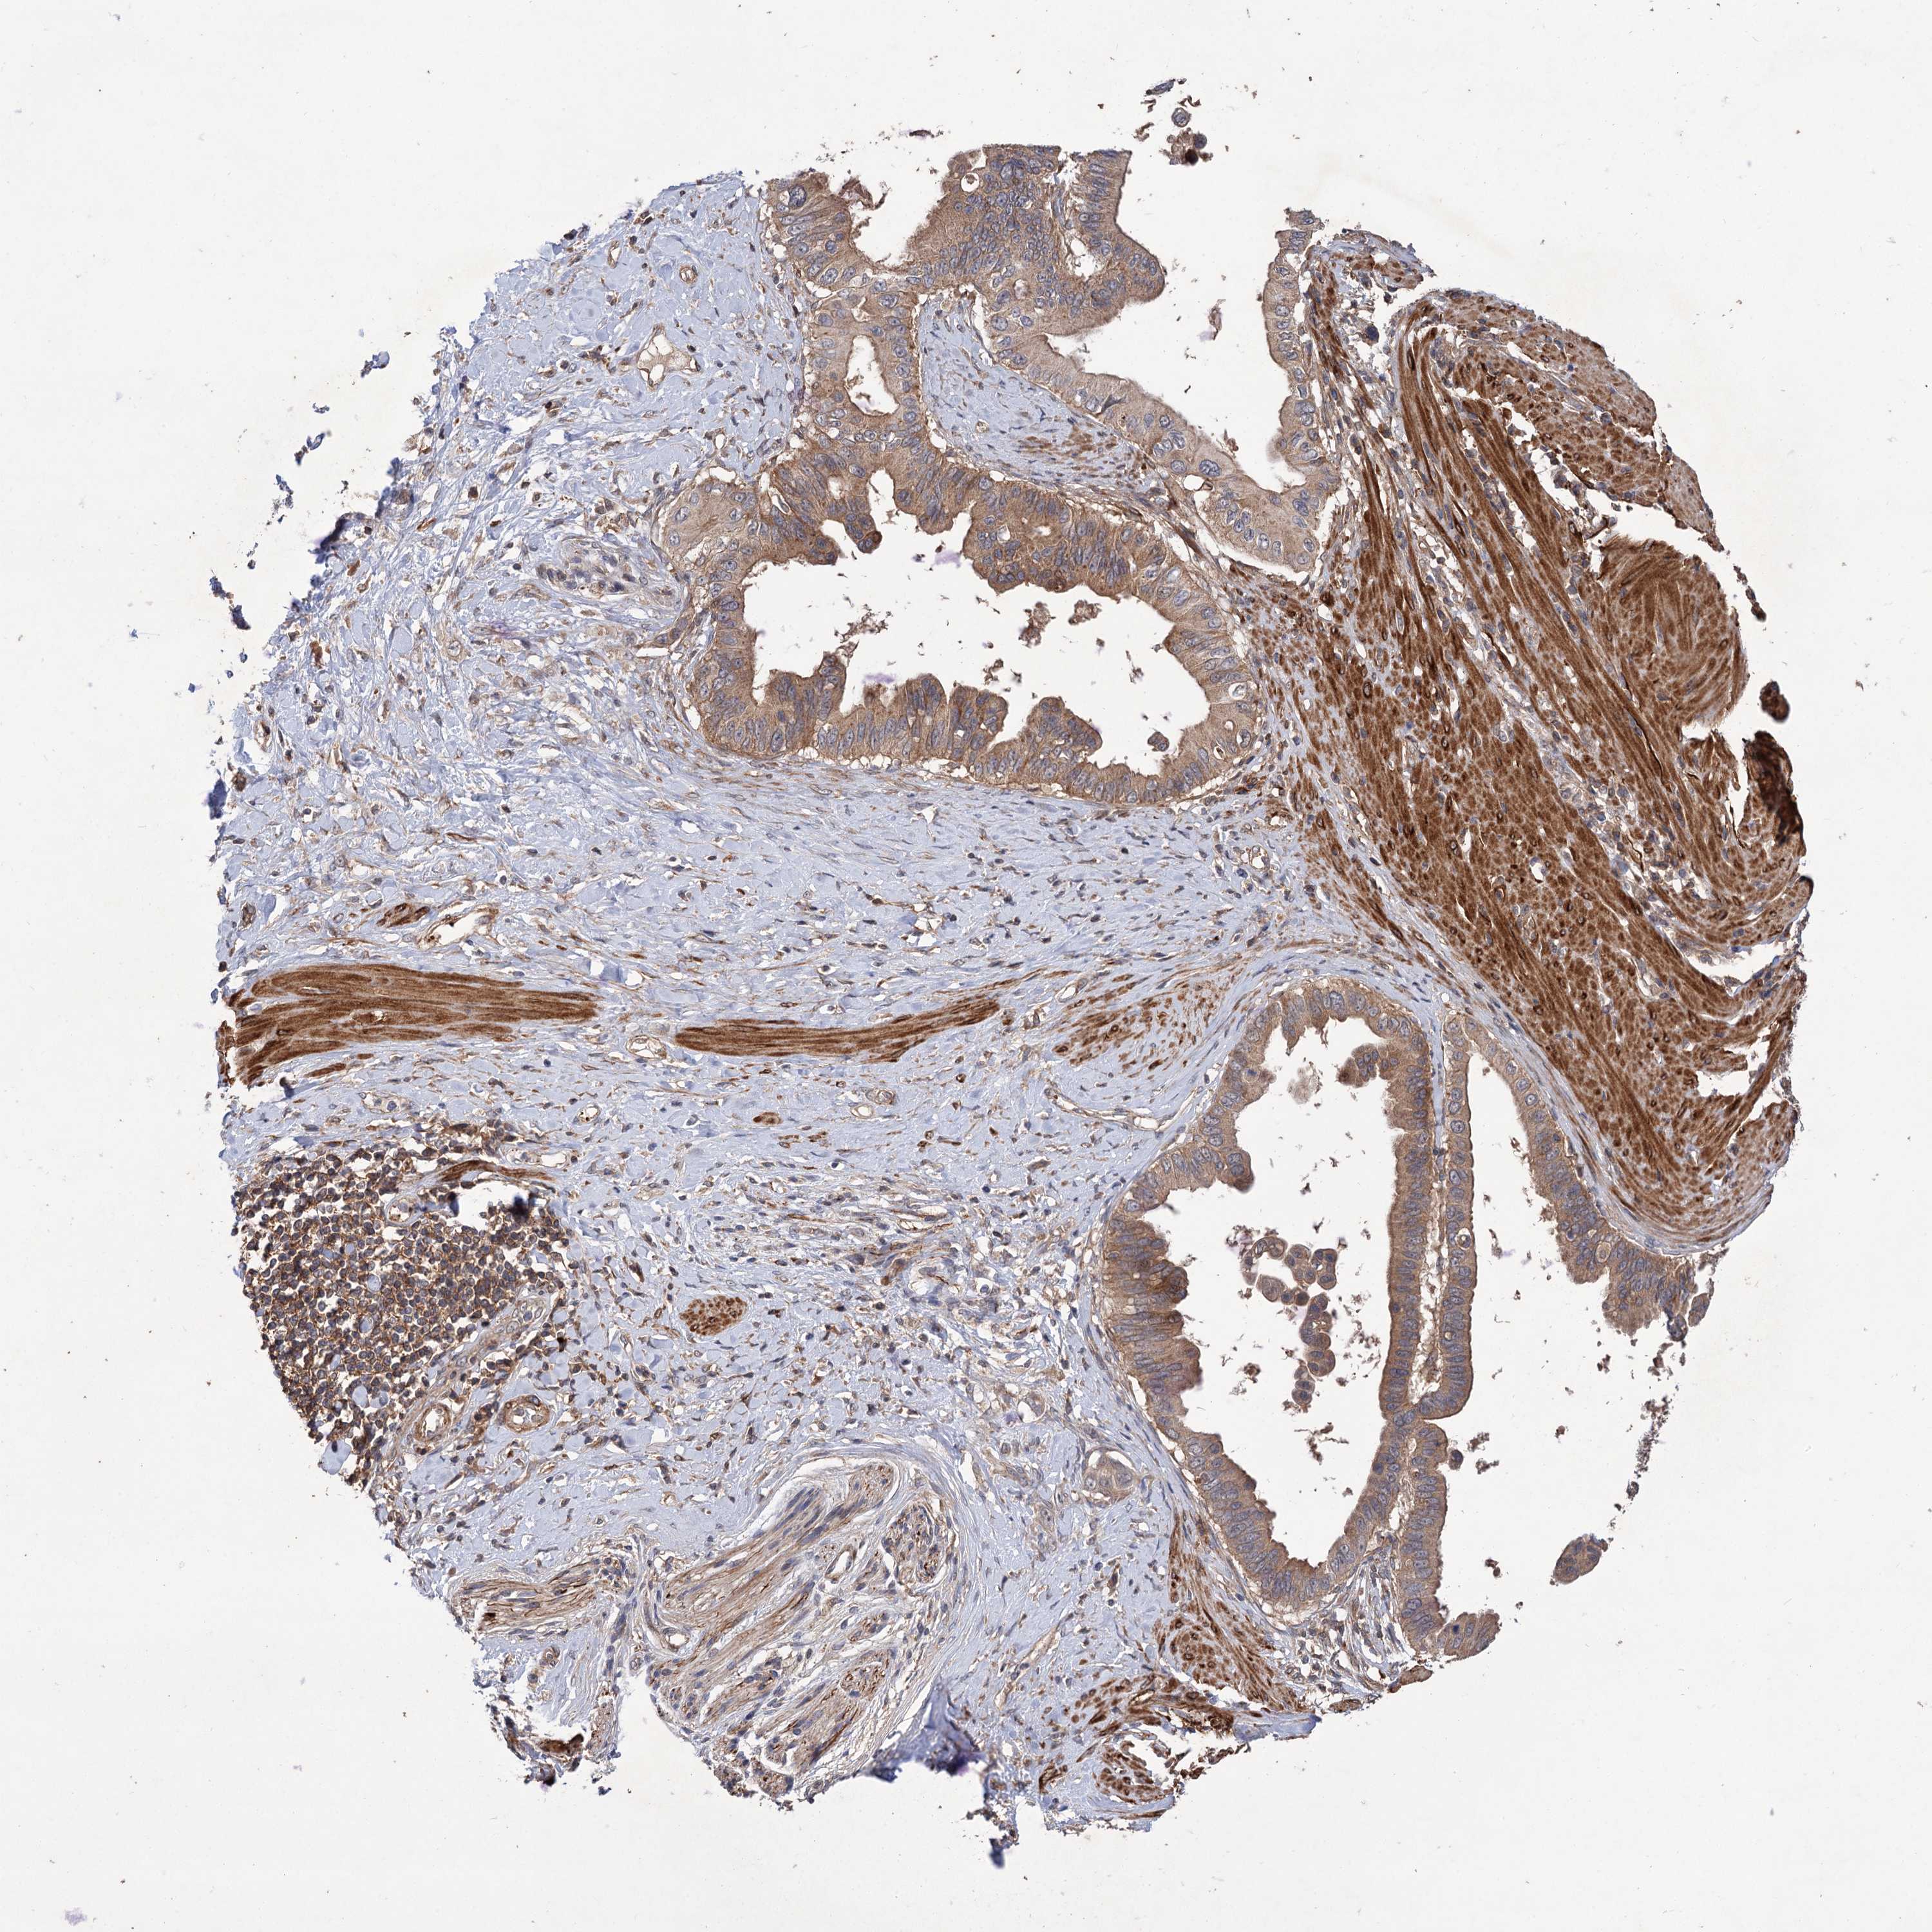

PANCREATIC CANCER - Protein expressioni

A mouse-over function shows sample information and annotation data. Click on an image to view it in a full screen mode. Samples can be filtered based on level of antibody staining by selecting one or several of the following categories: high, medium, low and not detected. The assay and annotation is described here.

Note that samples used for immunohistochemistry by the Human Protein Atlas do not correspond to samples in the TCGA dataset.

Antibody stainingi

Antibody staining in the annotated cell types in the current human tissue is reported as not detected, low, medium, or high, based on conventional immunohistochemistry profiling in selected tissues. This score is based on the combination of the staining intensity and fraction of stained cells.

Each image is clickable and will lead to virtual microscopy that enables deeper exploration of all samples and also displays staining intensity scores, fraction scores and subcellular localization as well as patient and tissue information for each sample.

Antibody HPA038850

Antibody HPA038851

Staining

High

Medium

Low

Not detected

Intensity

Strong

Moderate

Weak

Negative

Quantity

>75%

75%-25%

<25%

None

Location

Nuclear

Cytoplasmic/membranous

Cytoplasmic/membranous,nuclear

Adenocarcinoma, NOS